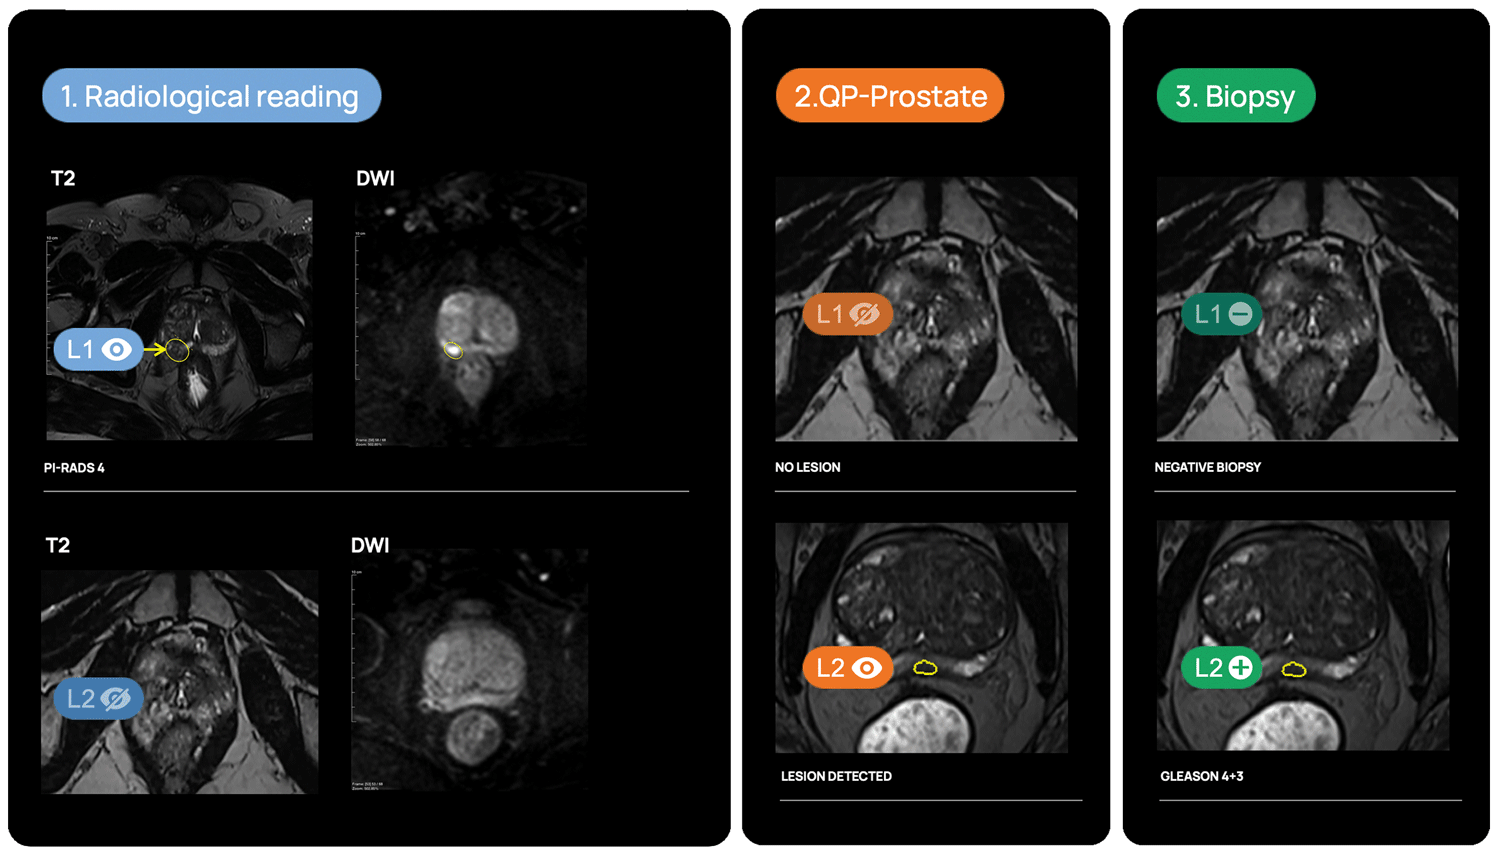

Lesion detection & diagnosis

QP-Prostate automatically identifies and highlights prostate regions suspicious for aggressive prostate cancer, assigning each a confidence-based classification score.

Fusion biopsy planning

QP-Prostate is fully integrated into most of the fusión biopsy devices, to allow a more accurate targeted biopsy.